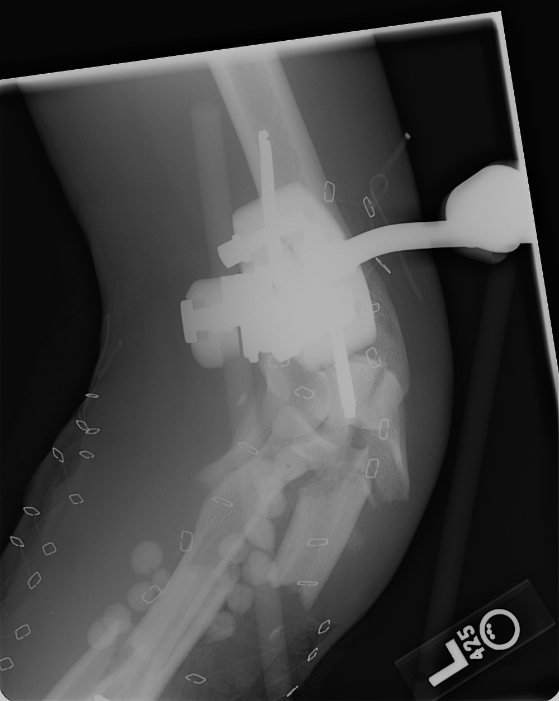

March 13, 2008 This shows the two plates inserted to hold the bone pieces in place. |

Marh 13, 2008 Here you can see the screws near his elbow. |